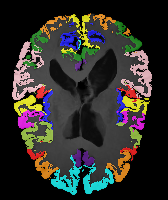

Results: All trained networks are evaluated using Dice overlap scores between predictions and the manual segmentations for the segmentation network, or between the warped moving segmentations and the target segmentations for the registration network. Tabs. 1 and 2 show results for the knee and brain MRI experiments respectively in Dice scores (%). Fig. 2 shows examples of knee MRI registrations and brain MRI segmentations.

Brain results: Dice scores for segmentation and registration increase by about 2.6 and 3.5 respectively for the cortical structures of the brain MRIs.

One-shot learning: In the one-shot experiments on both datasets, reasonable segmentation performance is achieved; moreover, DA increases the Dice score over unsupervised registration by about 2.7 and 1.8 on the knee and brain data respectively. This demonstrates the effectiveness of our framework for one-shot learning.

Qualitative results: DA achieves more anatomically consistent registrations than the mono-networks on the knee (Fig. 2) and Brain MRI samples (see supplementary material).